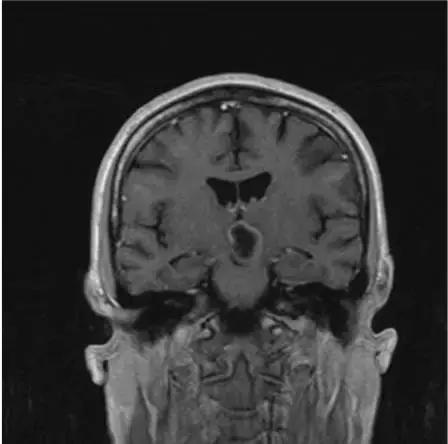

蛛网膜囊肿